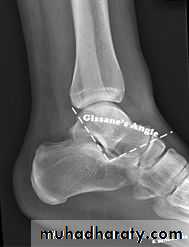

Calcaneal fracture, also known Don Juan fracture, is a fracture of the calcaneus. It is usually caused by a fall from height when one lands on their feet. These fractures represent approximately 2% of all fractures but 60% of tarsal bone fractures.